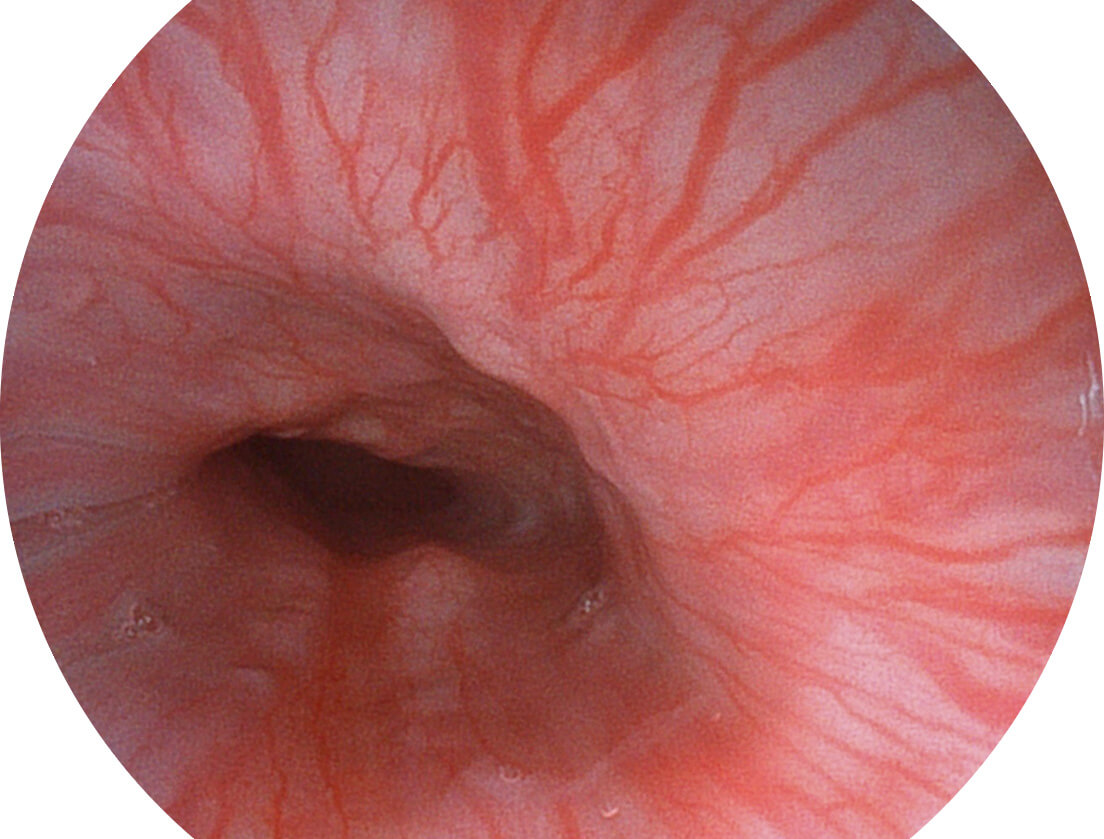

白光图像

SFI图像

Spectral Focused lmaging, SFI

图像具有高亮度、高黏膜血管颜色对比度的特点,且不改变粘液、食物残渣、粪便的基本颜色,可在中远景下进行观察,助力消化道早期疾病的诊断。